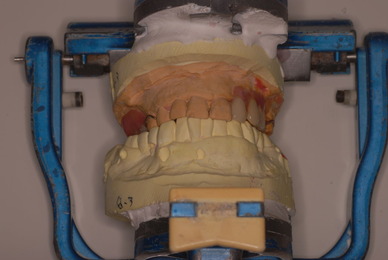

歯周病の疑いで東京のかなり遠方の方が来院されました。

驚くべきことですが、定期検診は受けていたそうです。しかしながら歯周病の指摘は受けたことがないそうです。

何故か?定期検診が虫歯のチェックのみになり、又肝心の歯周病の検査や歯周病の部分の予防や治療のためのブラシの使い方などを学んだ事がないのです。